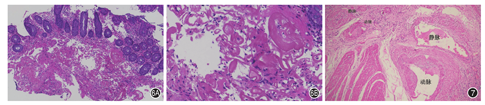

组织学表现为淋巴细胞性血管炎改变,常位于黏膜下或浆膜下层,动脉或静脉壁及其周围以淋巴细胞浸润为主;肠壁常见深溃疡形成,溃疡周围纤维组织增生伴炎性细胞浸润(图2A);慢性期可见孤立静脉血管全部或部分闭锁[7](图2B);溃疡旁黏膜可表现为慢性肠炎,小肠绒毛变短变平、隐窝分支、幽门腺化生等表现,偶可见急性缺血改变。肠白塞病常需与克罗恩病(Crohn′s disease,CD)进行鉴别,肠壁炎症反应及纤维化改变一般局限于溃疡周边,距离溃疡较远处,肠壁结构正常,一般无肉芽肿形成。

单一器官性血管炎(single-organ vasculitis,SOV)指累及单一器官的任何大小动脉或静脉的血管炎,且无系统性血管炎的临床或组织学证据。肠道是SOV的常见器官[12]。而累及肠道最常见的SOV是小肠结肠淋巴细胞性静脉炎(enterocolic lymphocytic phlebitis,ELP),它是一种局限于胃肠道的、以肠系膜静脉炎为特征的缺血性肠病,多发生于中老年患者,回肠和升结肠多见,一般不累及动脉,也不会有系统性血管炎的表现。最常见的临床表现是急性腹痛,也可表现为腹部肿块[13]。外科切除后一般不会复发[14]。组织学表现为淋巴细胞为主的炎性细胞浸润静脉壁,并在血管周围呈袖套状浸润,多累及小于2 mm的小静脉壁(图3A),也可以出现肉芽肿性和坏死性静脉炎[15]。缺血区域附近的肠系膜静脉周围淋巴细胞可呈新月形浸润[16]。受累肠段黏膜则呈慢性肠炎或缺血性改变(图3B)。